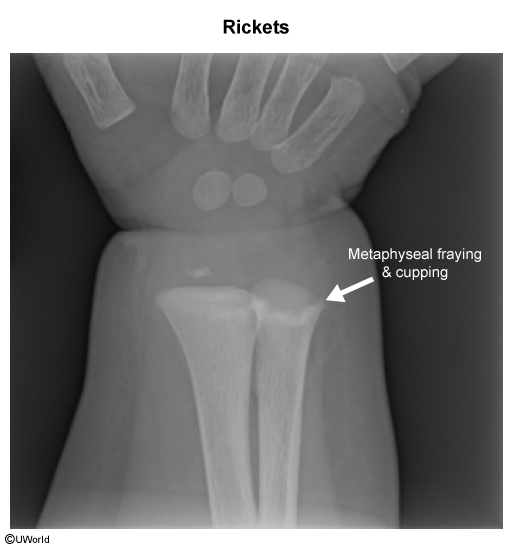

- Rickets is usually diagnosed through radiographic (X-ray) examination of the long bones.

- Findings may include:

- Osteopenic bone shafts (low bone density).

- Widened growth plates.

- Frayed and cupped metaphyseal ends (irregular and blurred bone ends).